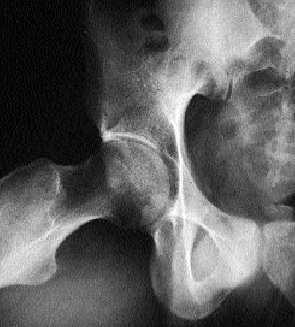

Fractura del cotilo o acetábulo sin desplazamiento

El error diagnóstico en esta fractura se produce por dos motivos: la fractura no se ve en las proyecciones habituales de pelvis o cadera y porque no se suele pensar en esta posibilidad diagnóstica. Se incluye, pues, en el grupo de las fracturas que nunca llegaremos a diagnosticar si no la sospechamos previamente.

Radiología

La exploración radiológica habitual de la cadera incluye las proyecciones A-P (es preferible efectuar la radiografía A-P de pelvis en lugar de cadera) y axial. En muchos casos estas proyecciones no demuestran la presencia de las fracturas no desplazadas del cotilo. Para verlas es necesario recurrir a dos proyecciones especiales que permiten ver con detalle las dos columnas óseas (anterior y posterior) que forman el cotilo.

1) Proyección de cadera oblicua interna a 45 grados también llamada alar (elevando 45 grados la cadera contraria).

2) Proyección de cadera oblicua externa a 45 grados también llamada obturatriz (elevando 45 grados la cadera lesionada).

Deberá sospecharse una fractura de cotilo en un paciente que ha sufrido un traumatismo importante, con dolor intenso e impotencia funcional de cadera, y las proyecciones radiológicas habituales no muestran lesiones óseas (fig. 12).

Fig. 12. Fractura del cotilo.